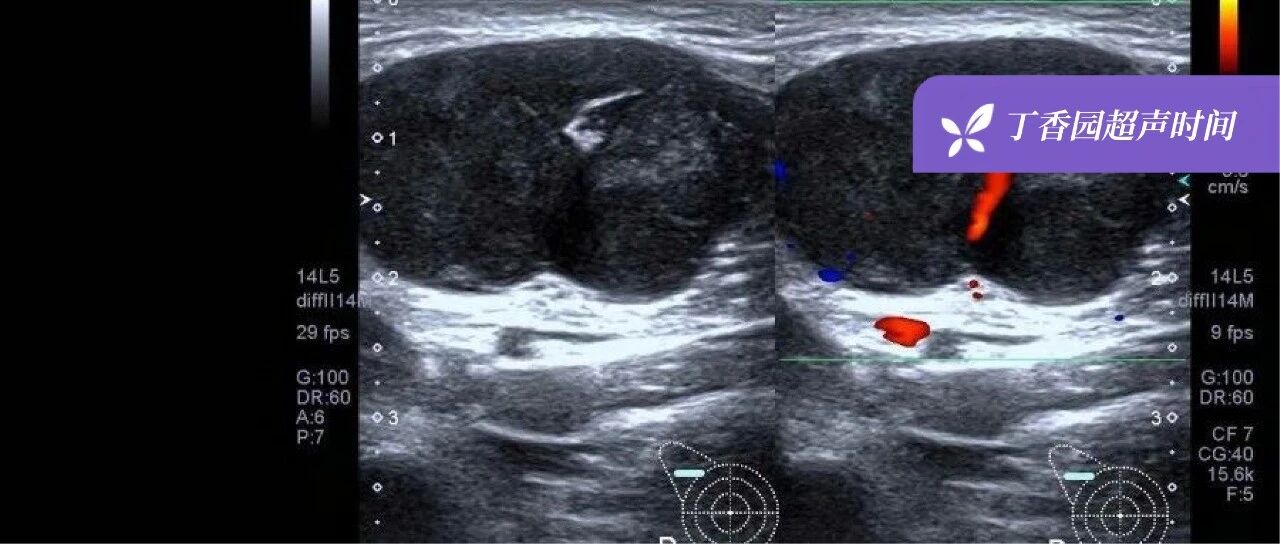

超声诊断「乳腺化生性癌」1 例